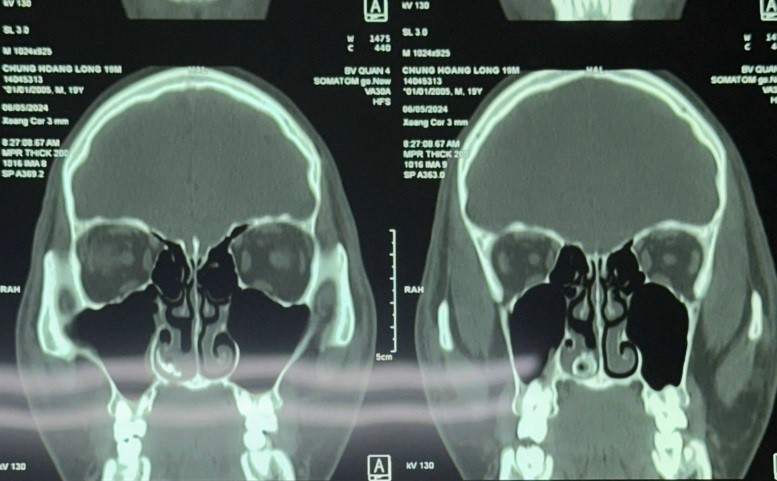

Bệnh nhân được chỉ định chụp CT scans và kết quả ghi nhận khối cản quang nghi ngờ dị vật trong hốc mũi bên phải.BSCKII Đào Duy Tường nhận định:” Đây là 1 trường hợp dị vật nằm trong hốc mũi quá lâu đồng thời mô hạt mọc rất nhiều tạo thành 1 khối mô chắc bao quanh che lấp dị vật nên tiên lượng khả năng bệnh nhân sẽ chảy máu nhiều trong quá trình lấy ra “